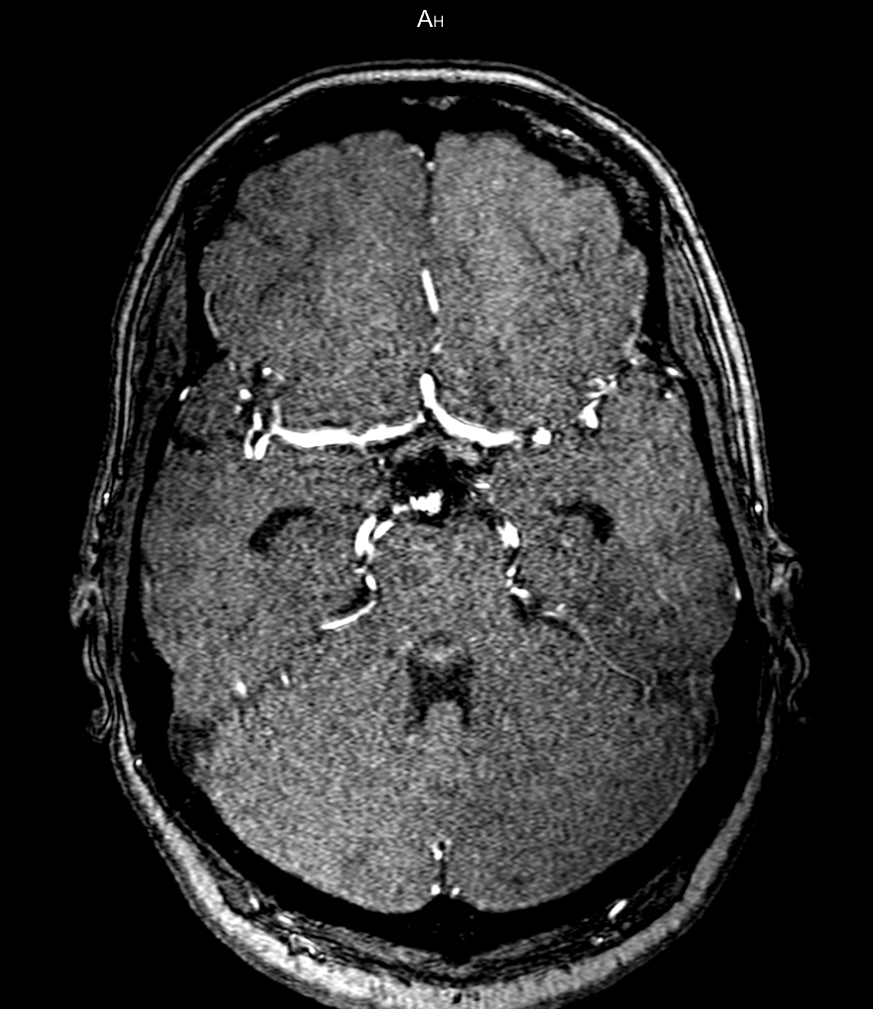

Deep learning approaches may help radiologists in the early diagnosis and timely treatment of cerebrovascular diseases. Accurate cerebral vessel segmentation of Time-of-Flight Magnetic Resonance Angiographs (TOF-MRAs) is an essential step in this process. This study investigates deep learning approaches for automatic, fast and accurate cerebrovascular segmentation for TOF-MRAs. The performance of several data augmentation and selection methods for training a 2D and 3D U-Net for vessel segmentation was investigated in five experiments: a) without augmentation, b) Gaussian blur, c) rotation and flipping, d) Gaussian blur, rotation and flipping and e) different input patch sizes. All experiments were performed by patch-training both a 2D and 3D U-Net and predicted on a test set of MRAs. Ground truth was manually defined using an interactive threshold and region growing method. The performance was evaluated using the Dice Similarity Coefficient (DSC), Modified Hausdorff Distance and Volumetric Similarity, between the predicted images and the interactively defined ground truth. The segmentation performance of all trained networks on the test set was found to be good, with DSC scores ranging from 0.72 to 0.83. Both the 2D and 3D U-Net had the best segmentation performance with Gaussian blur, rotation and flipping compared to other experiments without augmentation or only one of those augmentation techniques. Additionally, training on larger patches or slices gave optimal segmentation results. In conclusion, vessel segmentation can be optimally performed on TOF-MRAs using a trained 3D U-Net on larger patches, where data augmentation including Gaussian blur, rotation and flipping was performed on the training data.